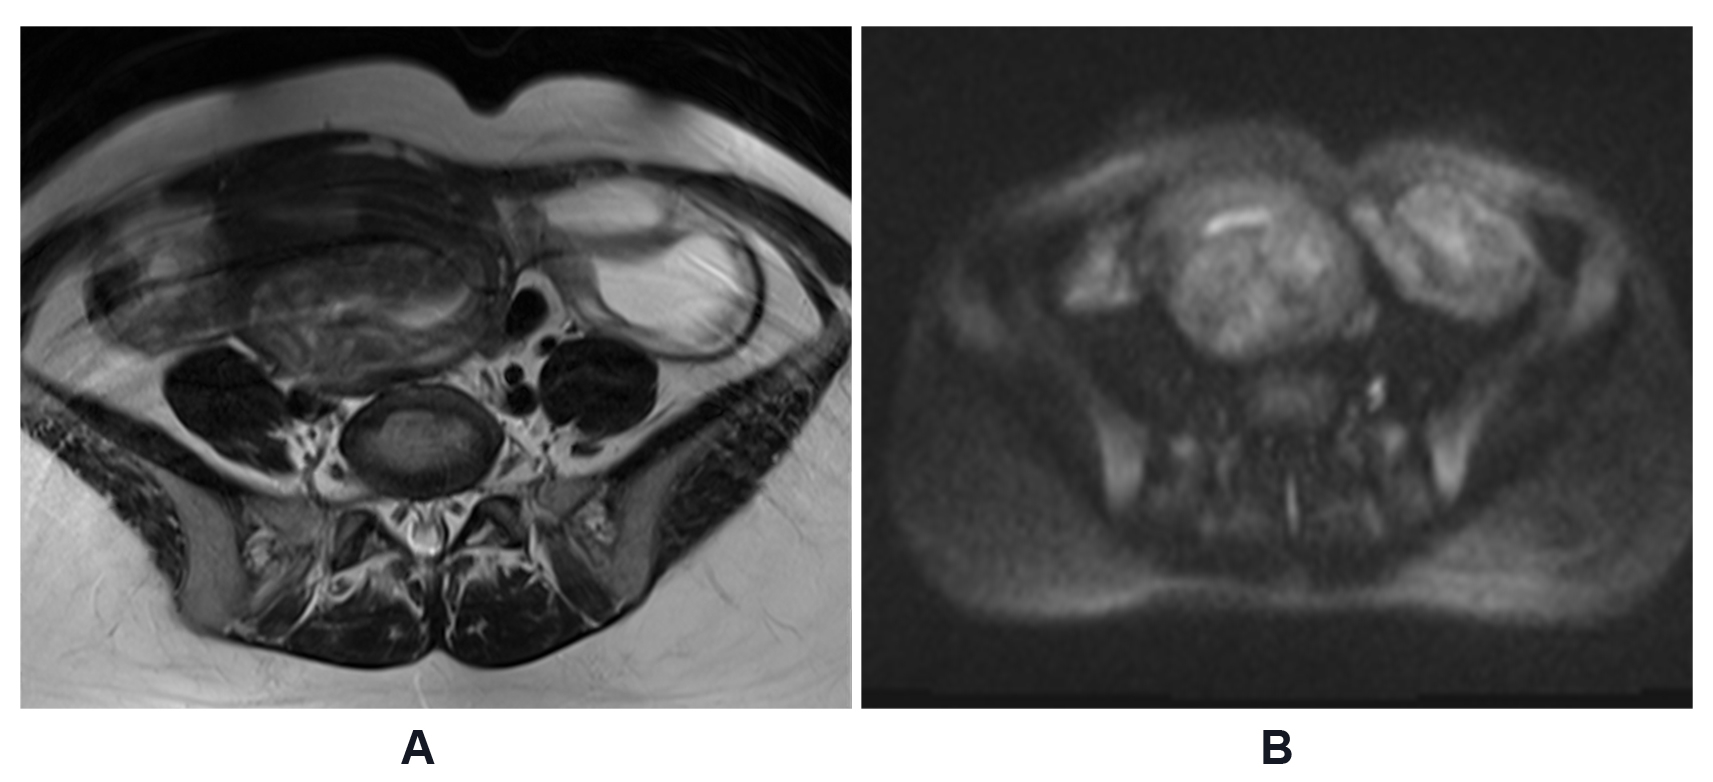

A transthoracic echocardiogram revealed a large mass occupying almost the entire right atrium, extending into the inferior vena cava. A CT scan showed a large, low attenuation, and minimally enhanced mass extending from the right atrium into the inferior vena cava and right hepatic vein, possibly invading segments VII-VIII of the liver (Figure 1). Abdominal CT and MR images revealed multiple degenerating uterine fibroids, bilateral dilated uterine tubes, and mild right hydronephrosis (Figure 2).